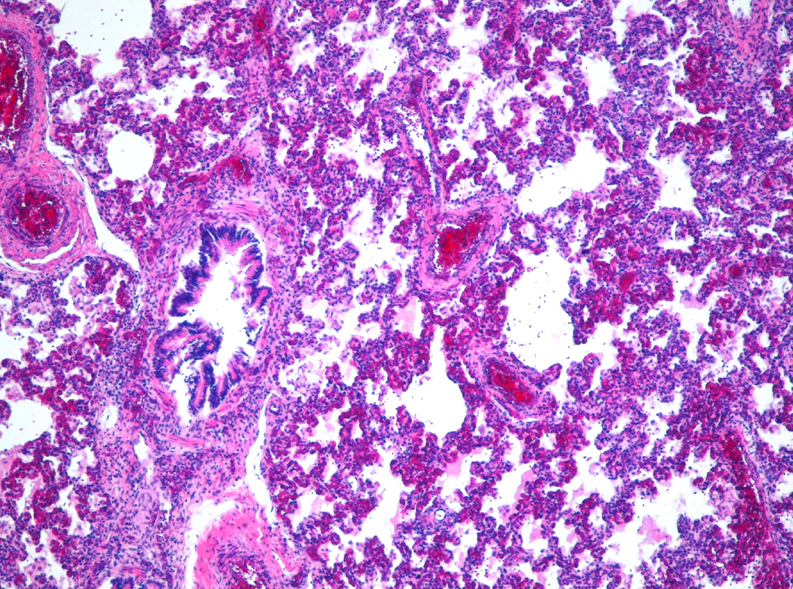

Identify this lesion

What is the most common cause?

(name all that apply)

Interstitial pneumonia

Identify lesion:

Who is most affected by this lesion

and what are the syptoms?

Children, elderly patients

Symptoms: